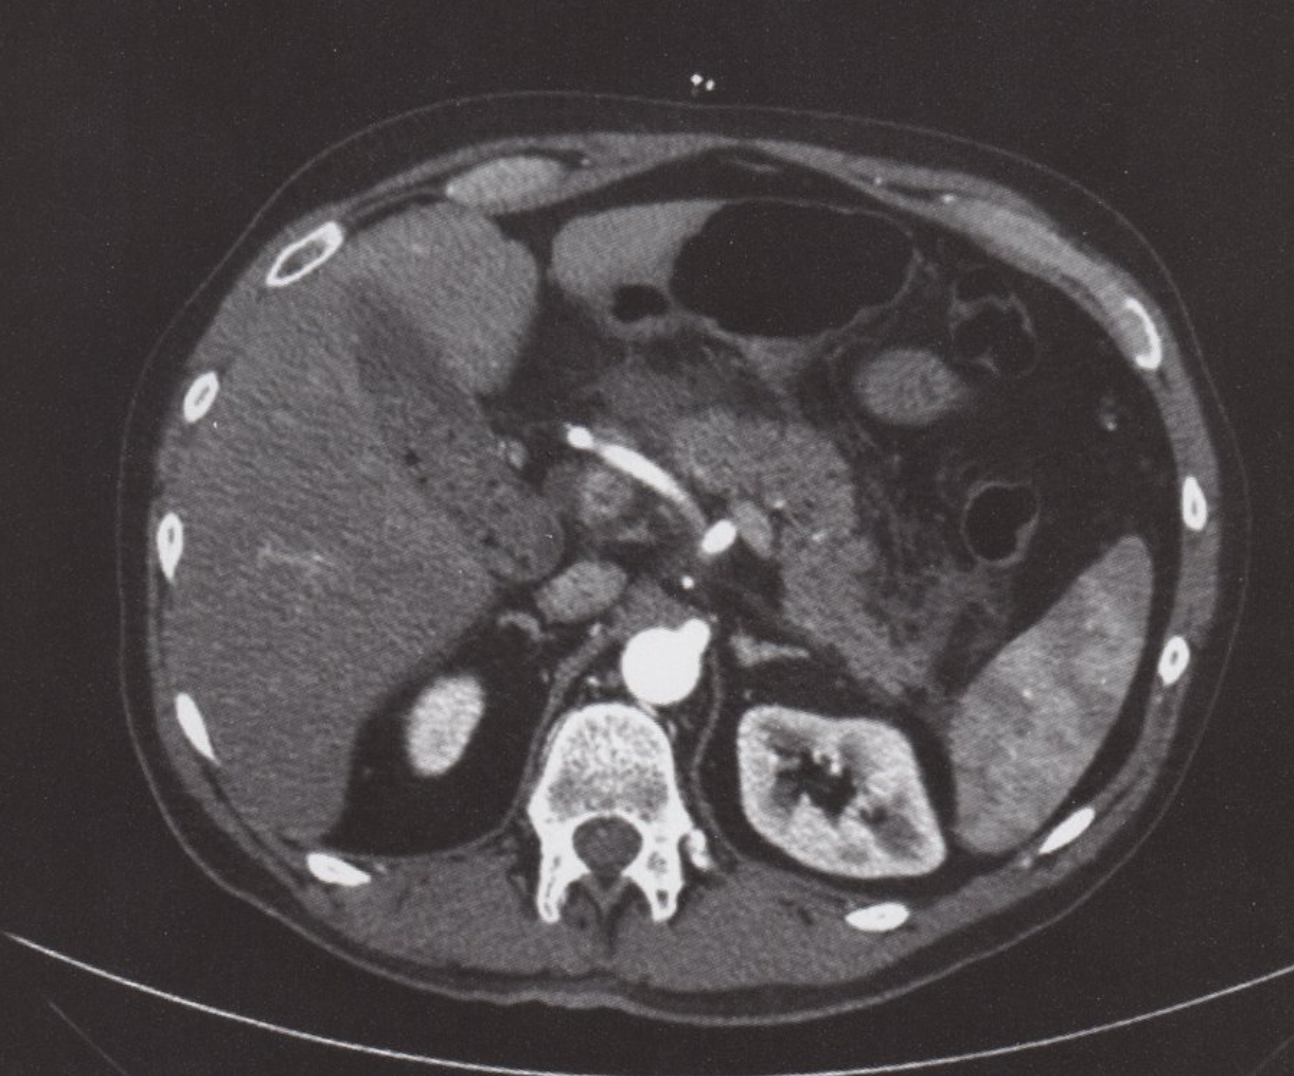

TDM de l’abdomen (avec produit de contraste ; plan axial)

Une collection liquide péripancréatique aiguë homogène non encapsulée (APFC) sans composants solides est visible. L’aspect est caractéristique de la pancréatite interstitielle aiguë (non compliquée). Un échouage liquidien et graisseux peut être observé en avant du pancréas ainsi que dans les espaces pararénaux (flèches rouges). Il existe également du liquide périrénal (flèche blanche). Le tissu pancréatique (flèche en pointillés ; P) est rehaussé de manière homogène, sans signe de nécrose tissulaire.

Les APFC peuvent être uniques ou multiples et se développent généralement au début de la pancréatite aiguë. La persistance pendant plus de 4 semaines augmente la probabilité de développement d’un pseudokyste.